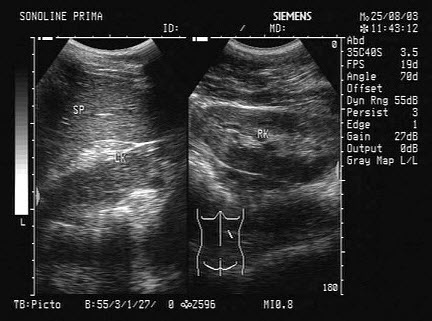

179、单项选择题

如图所示,双肾结构清晰,左肾体积小,该病例最可能诊断是()

A.肾发育不良

B.肾萎缩

C.慢性肾炎

D.肾结核

E.慢性肾衰

180、单项选择题 急性胆囊炎USG表现中,哪项不正确()